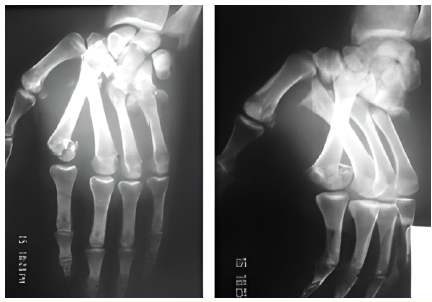

Case Report

A Rare Case of Divergent Carpo-Metacarpal Fracture-Dislocation in a Young Athlete

Mohamed Rida El Galiou, El Yazid Houass and Mohamed Salah Berrada. 14(8): 01-04.